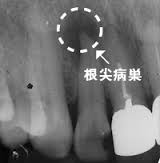

虫歯が進行して歯の神経を侵し,根の先端部分(根尖部)にまで虫歯菌が達すると、根の外にまで病変が拡大し、根尖病変が生じます。根尖病変は、根の先の黒い影としてエックス線写真でわかります。 根の中や外側に棲息する虫歯菌に対して、からだの抵抗力(免疫力)が働いて炎症反応が起こり、その結果 根尖病変ができます。神経を取る治療をした歯も根の中に虫歯菌が潜んでいる可能性があります。体は根尖に虫歯菌を閉じこめようとしますが、糖尿病などでからだの抵抗力が低下していると、虫歯菌が周囲の組織に拡大し血液中に入り込んで全身に拡がり、菌血症となって生命の危険が生じる事態となります。特に糖尿病の方は、口の中だけを見てもわからないので、定期的なレントゲン検査と早期の治療が必要です。